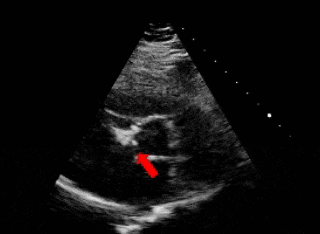

右盘展开

右盘面展开后

前推钢缆使其成型

超声下可见双盘面骑跨

释放后评估

封堵器形态良好,基本无残余分流